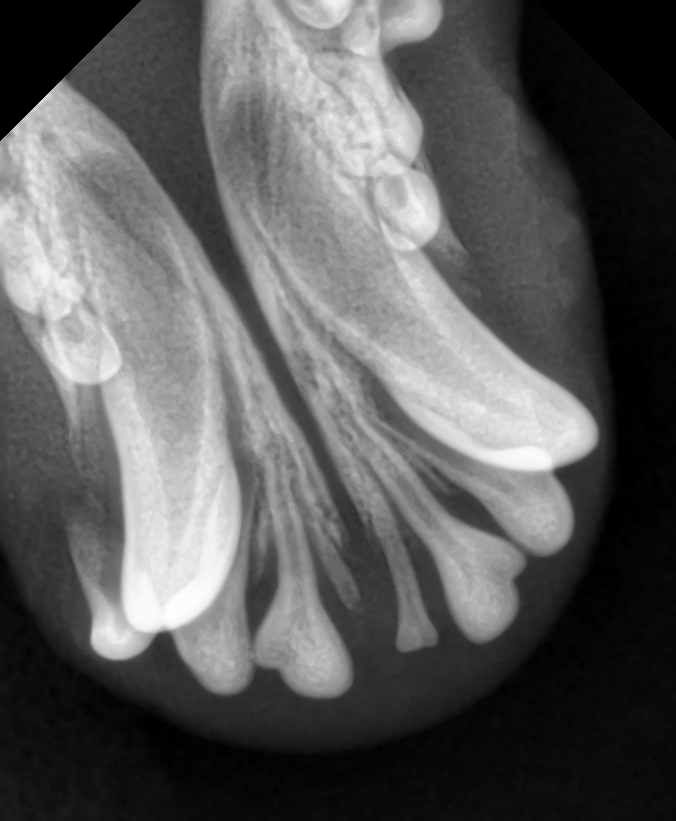

Рентгеновский снимок нижней челюсти нашего щенка. 4 резца - спутник ланца. По моим предположениям, это не связанный с ланцем признак, а одна из частей пазла, который формирует в итоге ланц.

-2

Рентгеновский снимок верхней челюсти нашего щенка. Огромный толстый лежащий корень ланца хорошо видно. А теперь представьте операцию по его перемещению вертикально вниз. В этом конкретном случае это что-то из ряда фантастики.